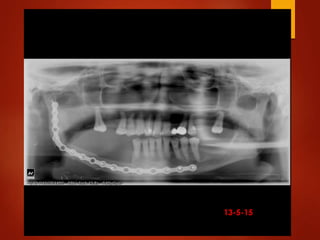

El documento es un registro médico odontológico que muestra las fechas de las visitas de un paciente al centro de salud El Raval, incluyendo exámenes y tratamientos realizados como la extracción de cálculos salivales en abril y mayo de 2012.